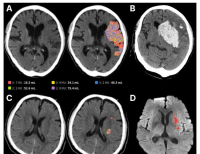

- 제이엘케이, 비조영 CT 기반 뇌경색 병변 검출 AI 성과 논문 게재 … 손상범위 정량화, 예후예측 가능

- 의료 AI 전문기업 제이엘케이가 개발한 뇌경색 병변 검출 AI 모델이 대규모 임상 검증을 통해 신뢰성을 입증했다.이번 성과는 SCI급 국제학술지 ‘Frontiers in N...